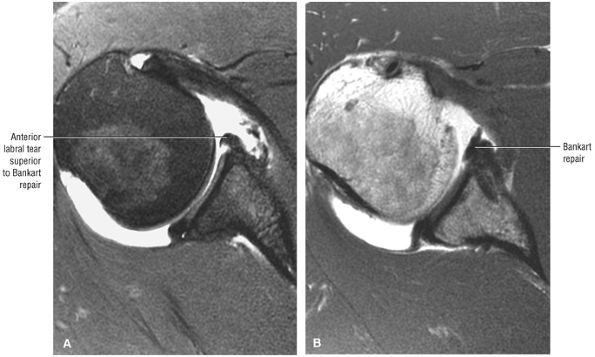

Postoperative evaluation of repaired labral capsular structures and/or strictures, recurrent rotator cuff tears or partial tears, and displaced hardware

ABER (abduction external rotation) images in conjunction with MR arthrography are helpful in evaluating the postoperative labrum and nondisplaced (e.g., Perthes) labral tears.